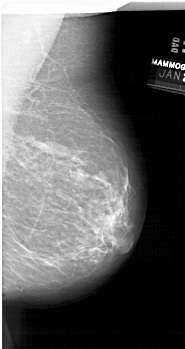

A_1679_1.LEFT_MLO

LEFT_MLO LINES 6781 PIXELS_PER_LINE 3631 BITS_PER_PIXEL 12 RESOLUTION 43.5 OVERLAY